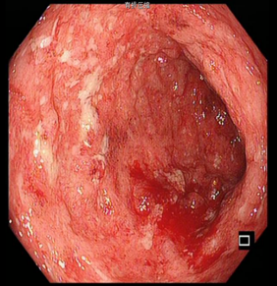

该患者入院时溃疡性结肠炎诊断明确,查血提示WBC16000/ml、HGB130g/L 、CRP29mg/L、ESR44mm/h、TP61g/L、ALB27g/L、pre-ALB120g/L。查ANA、ANCA、结核、EB、CMV(-)。肠镜提示患者全结肠粘膜连续性病变、弥漫性溃疡、粘膜充血水肿并覆白色脓液,结肠袋消失。CT提示全结肠弥漫性水肿、增厚,肠管僵硬。分析该患者溃疡性结肠反复发作、逐渐加重,并且应用美沙拉嗪、激素、免疫抑制剂及单抗治疗效果不佳,所以有全结肠切除的指征。但患者近3月内应用过类克及激素治疗,此时进行手术,势必会出现术后吻合口瘘、腹腔感染等严重并发症。

肠镜下肠粘膜表现